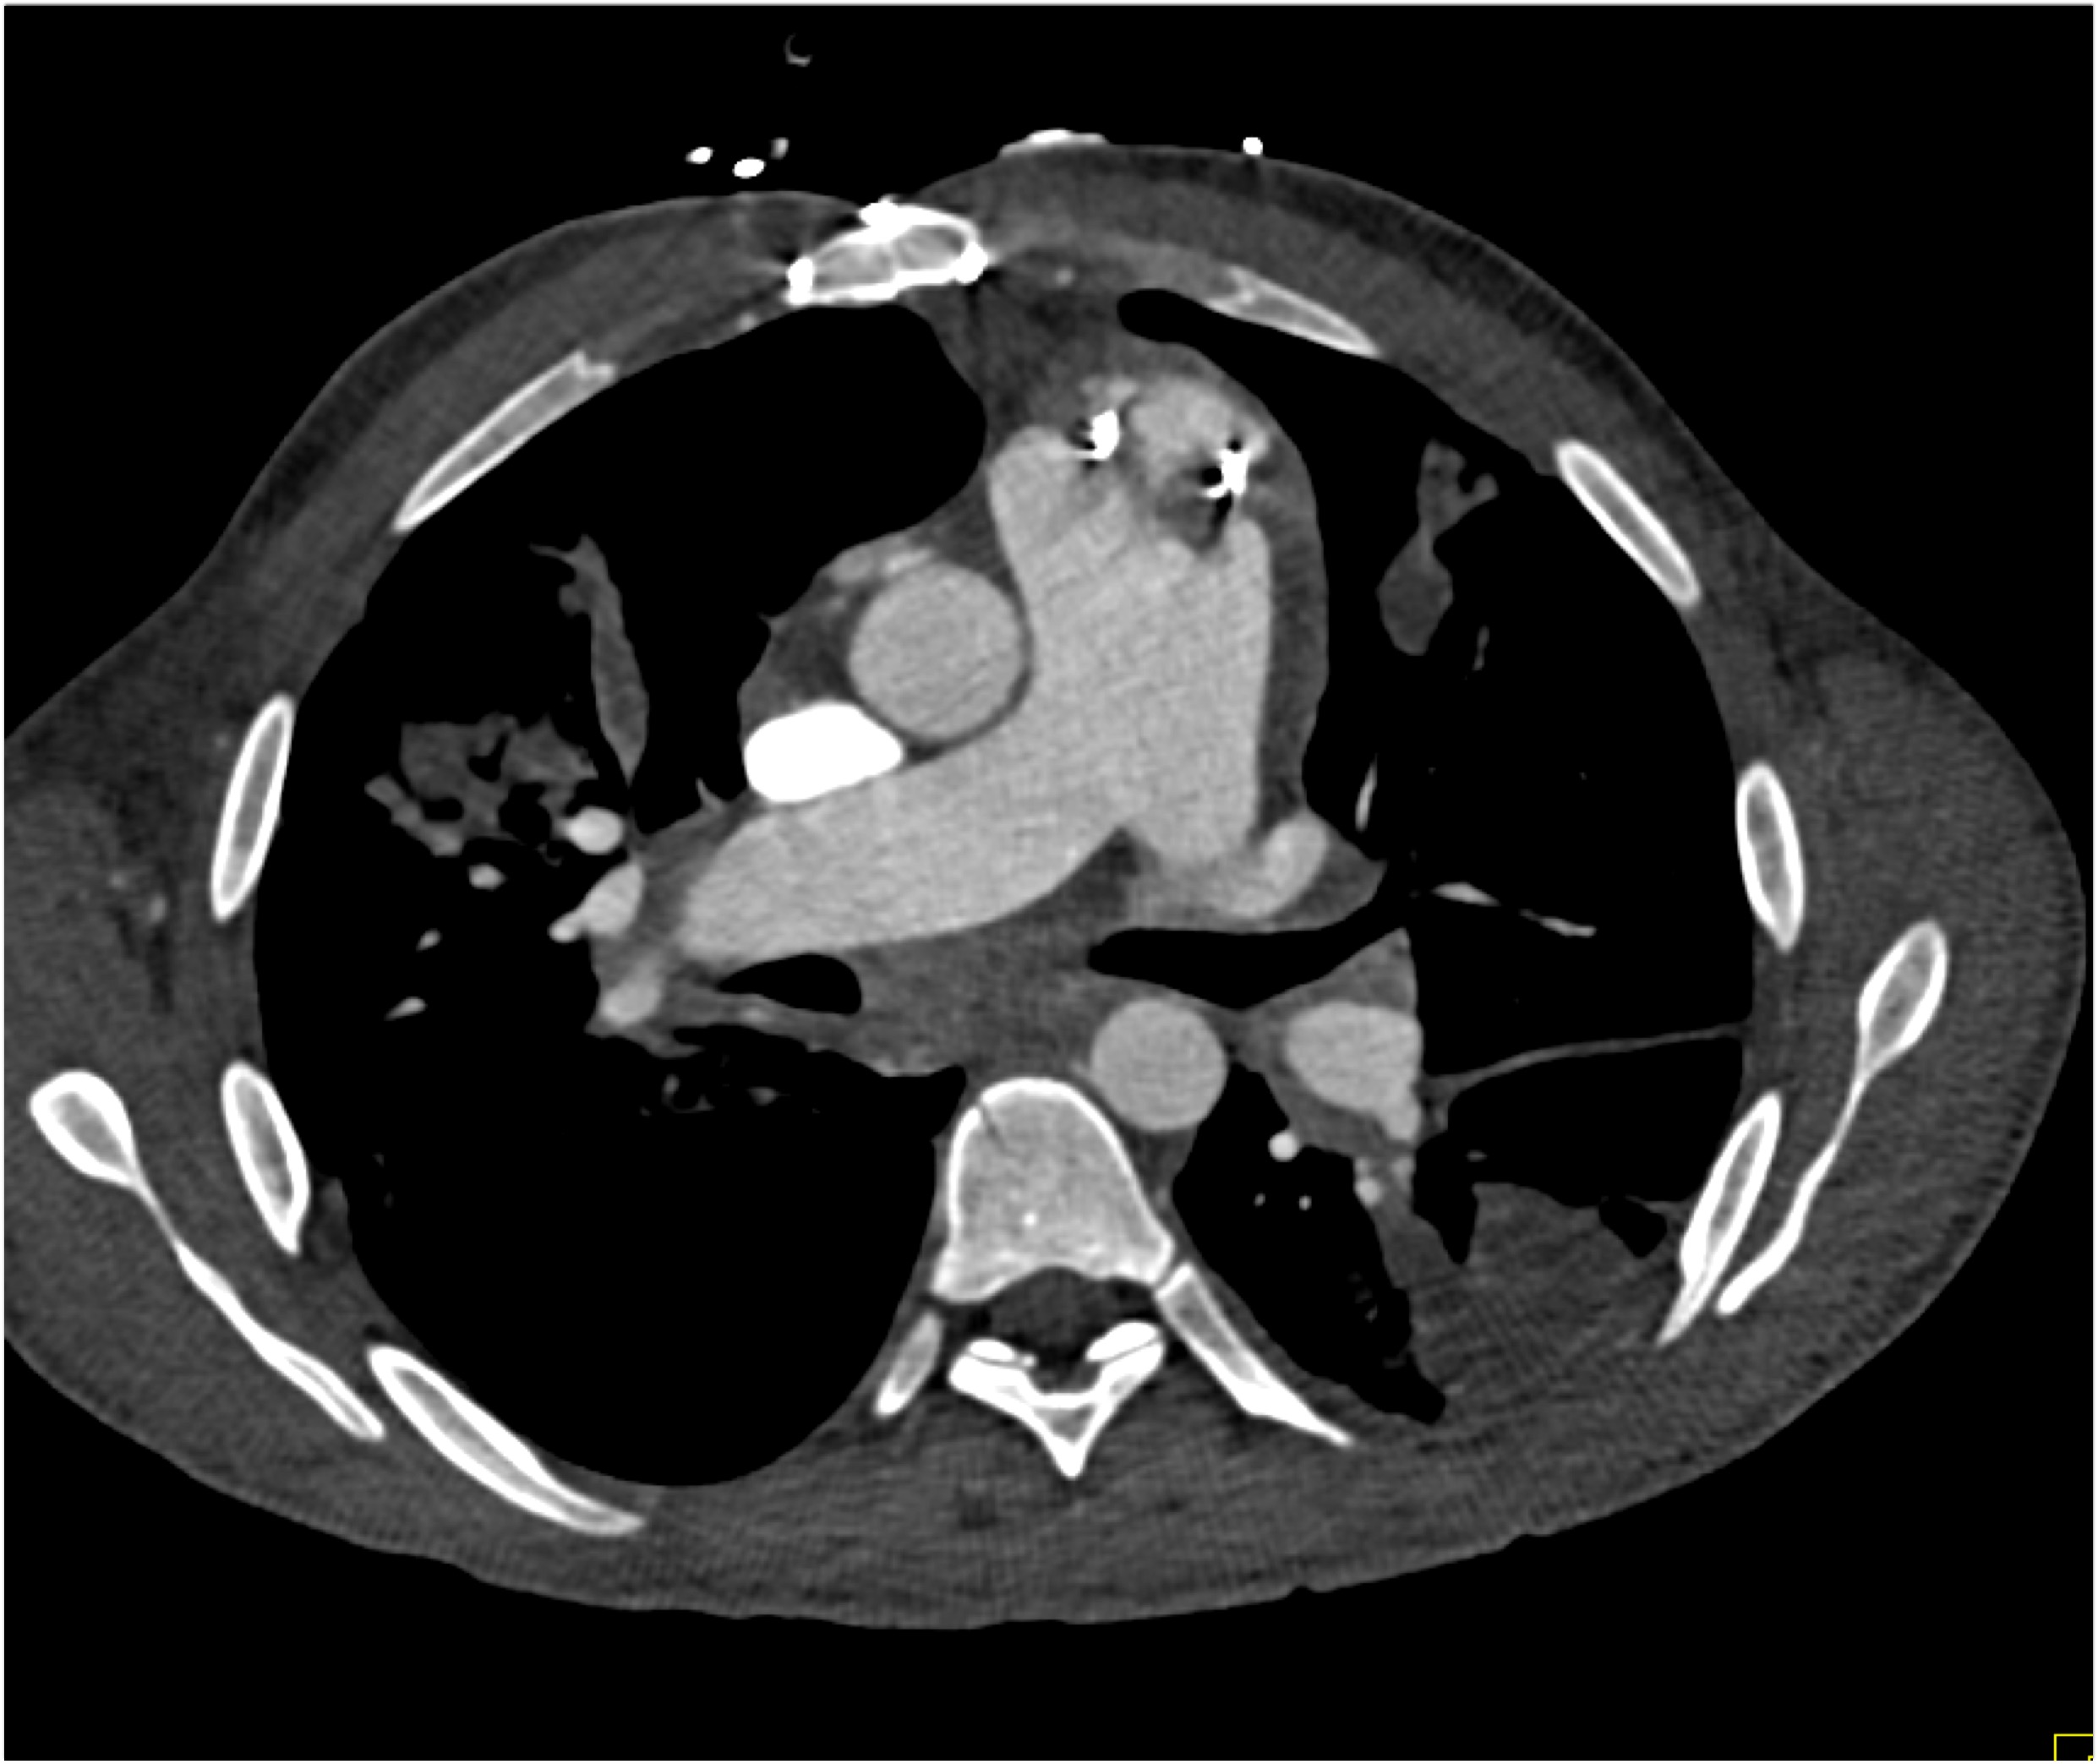

8) The most likely diagnosis in this case is?

clear cell renal cell carcinoma

large B-cell lymphoma

seminoma

renal abscess